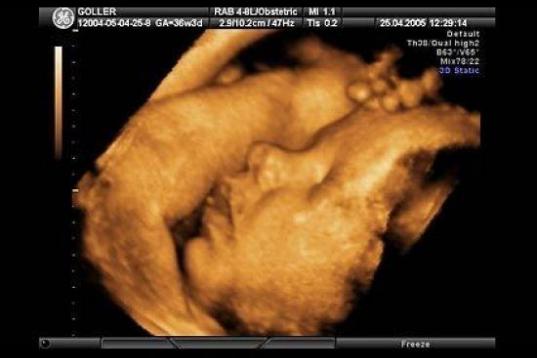

En esta galería puedes ver en fotos como es el desarrollo de un feto de semana en semana:

Desarrollo del feto, en fotos